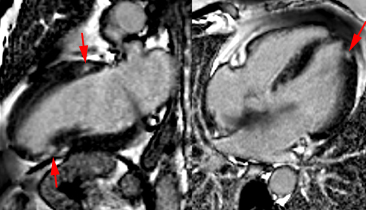

– Insuffisance tricuspide : intérêt de l’IRM dans la maladie d’Ebstein mais pas de quantification aisée de la PAP systolique comme en écho-doppler.

– Insuffisance pulmonaire : quantification de la fraction de régurgitation pulmonaire fiable (anciens Fallots…)

– Sténose pulmonaire : L’IRM aide à discriminer les atteintes valvulaires des obstacles sous ou sus valvulaires dans les cardiopathies congénitales.

– Les abcès annulaires infectieux ou froids calcifiés constituent de bonnes indications pour l’IRM cardiaque.